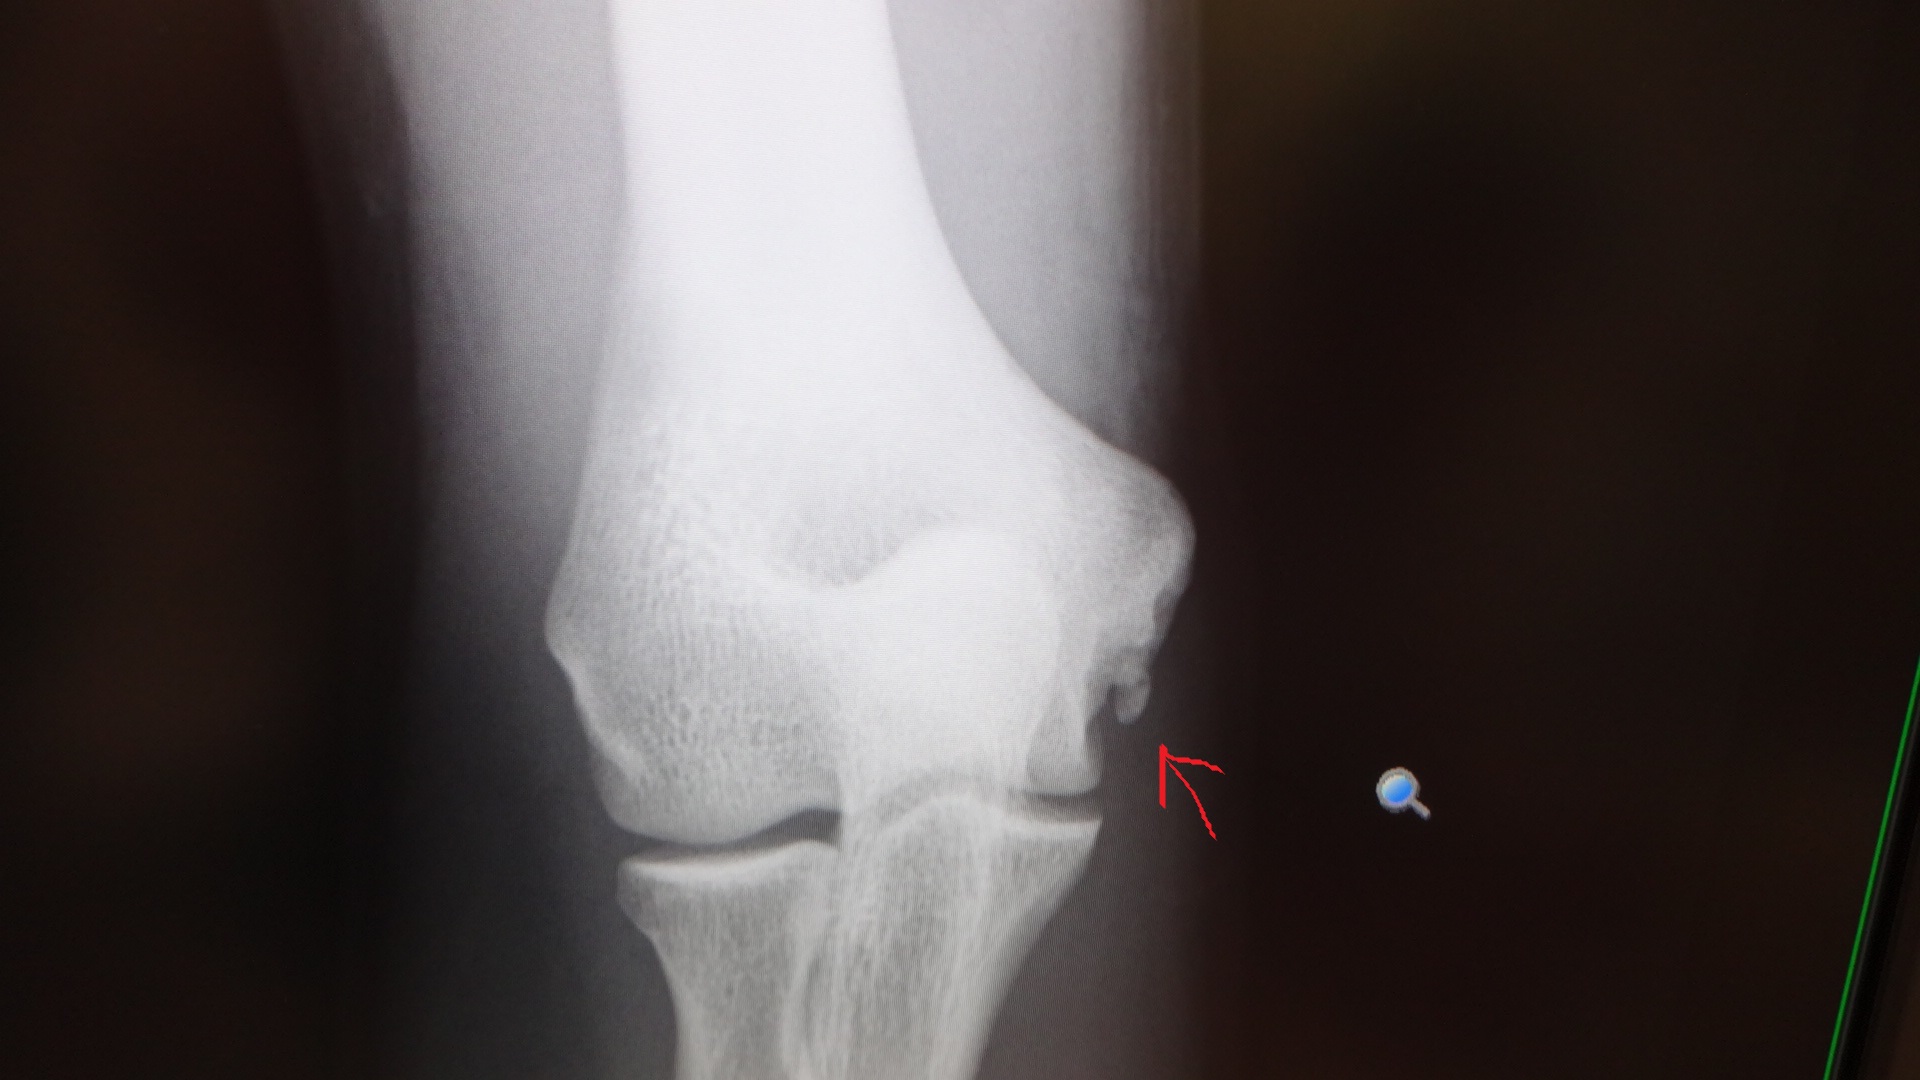

*今回のブログには、肘のレントゲン写真が載っていますので、

苦手な方は、スルーして下さい。

5月の時の肘のレントゲン写真は、

こちら。

矢印の所に、突起物が有ります。

靭帯が切れて、剥がれ掛かっているそうです。

この時は、約1ヶ月の休息期間を置きまして、

最後の大会に臨んだのですが、

やっぱり、無理をしていた様です。

今回の受診で、再度、レントゲンを撮ったのですが、

今回は、

この様になっていました。

突起物も、大きくなっていて、

かなり悪化しているとの事。

ピッチングは勿論の事、

バッティングも、行ってはいけないそうです。